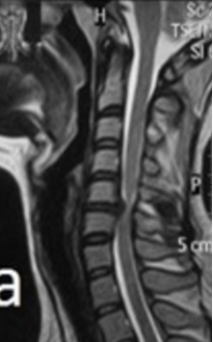

hernia de disco

aonde esta a hernia?

que exame é esse?

A

Hérnia de disco C5 - C6: RM em T2